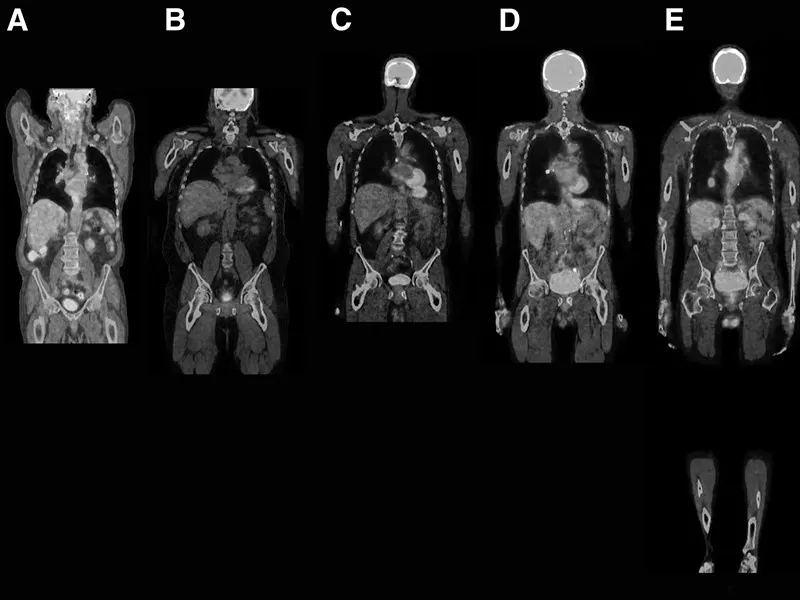

Tüm vücut MR, genellikle hastalıkların erken teşhisi ve yayılımının değerlendirilmesi amacıyla çekilir. Özellikle kanser taramaları, inflamatuar hastalıklar, enfeksiyonlar ve dejeneratif hastalıkların tespitinde kullanılır. Ayrıca, vücutta mevcut olan anormalliklerin detaylı bir şekilde incelenmesi için de tercih edilir.

Tüm vücut MR, kanser şüphesi olan hastalarda, inflamatuar hastalıklarda, enfeksiyonların yayılımını belirlemek için ve dejeneratif hastalıkların teşhisinde kullanılır. Ayrıca, kronik ağrıların kaynağını tespit etmek, sinir sistemi hastalıklarını ve damar problemlerini değerlendirmek amacıyla da uygulanabilir.

Tüm vücut MR ile kanser türleri, tümörlerin yayılımı, inflamatuar hastalıklar, enfeksiyonlar, dejeneratif hastalıklar, sinir sistemi bozuklukları ve damar hastalıkları teşhis edilebilir. Bu yöntem, özellikle erken teşhis gerektiren hastalıklarda büyük önem taşır ve doktorların doğru tedavi yöntemini belirlemelerine yardımcı olur.